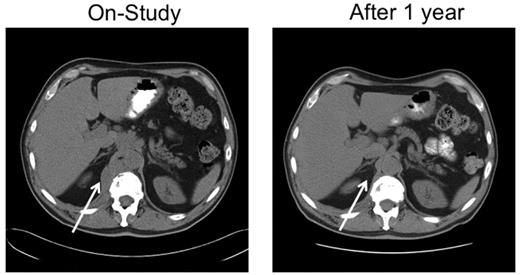

A 67-year-old man with stage IVA diffuse large B-cell lymphoma. He was treated with rituximab, cyclophosphamide, vincristine and prednisone × 6 with an initial complete response, only to relapse 7 months later. He responded to salvage chemotherapy and received an autologous stem cell transplantation with a 6-month TTP. After failing single-agent rituximab, he joined this study. He responded to tipifarnib 300 mg twice daily. Because of myelosuppression, the dose was reduced to 100 mg twice daily. He maintained remission for 25 months before progressing on therapy. Tumor biopsies before and after tipifarnib demonstrated low bcl-2 protein tumor content at baseline with a marked increase in Bim isoforms and decrease in p-ERK after tipifarnib (patient 6; Figure 2C).